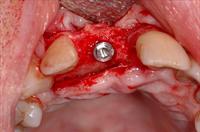

![]() 8. The screw was removed, and a drill guidance system was used to place a 4mm wide platform Branemark implant. |